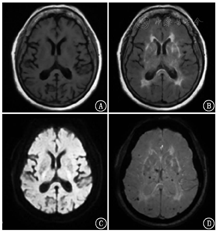

患者女,73岁,受教育程度:6年(小学文化)。因"出现幻视半年余伴认知障碍(主诉看到已过世或不存在的人及经常不能认出丈夫)、进行性记忆下降3年余"就诊。体格检查:血压130/80 mmHg(1 mmHg=0.133 kPa),双侧瞳孔等大正圆,反应迟钝,双侧鼻唇沟等深,四肢肌张力增高,双上肢和双下肢腱反射未引出,无颈项强直,Kernig征阴性。神经精神心理学评估:计算力明显下降,不能配合完成神经精神量表检查。既往史:高血压10余年,控制可,无糖尿病、症状性脑卒中等病史。实验室检查:甲状腺功能正常,叶酸、血清维生素B12正常,梅毒筛查甲苯胺红不加热血清试验(toluidine red unheated serum test, TRUST)阴性。头颅MRI示:T1加权成像(weighted imaging, WI)未见明显异常(图1A);T2WI示多发非对称性白质高信号病灶并延伸至皮质下白质(图1B);弥散WI(diffusion WI, DWI)未见明显异常(图1C);磁敏感WI(susceptibility WI, SWI)示颅内散在皮质、皮质下多发微出血病灶(图1D)。18F-脱氧葡萄糖(fluorodeoxyglucose, FDG)及淀粉样蛋白显像剂18F-florbetapir[AV-45;AV-45显像得到本院伦理委员会的批准(批准号:2018-191),患者签署知情同意书]由本院核医学科自制,PET/CT(德国Siemens Biography mCT)显像结果如下:CT示右侧脑室旁腔隙性脑梗死灶(图2A);双侧顶叶、双侧枕叶和右侧额叶弥漫性FDG代谢轻度减低(图2B);双侧额叶、颞叶、顶叶和枕叶皮质见淀粉样蛋白沉积(图2C)。根据脑淀粉样血管病(cerebral amyloid angiopathy, CAA)波士顿诊断标准[1,2],最终临床诊断为CAA。

本例患者年龄73岁,缓慢起病,临床表现以幻视半年余伴认知障碍为主;其头颅MRI T2WI示多发非对称性白质高信号病灶并延伸至皮质下白质,SWI示颅内散在皮质、皮质下多发微出血病灶,符合影像学诊断标准;患者其他常规检查已排除感染及肿瘤病史,符合CAA波士顿诊断标准全部表现。因为患者认知功能下降,还需要鉴别诊断是否合并AD。首先,未见本例患者有明显海马萎缩,与AD不符;其次,Aβ沉积以双侧枕叶为著,而AD患者较少累及枕叶;最后,本例患者FDG代谢轻度减低而认知功能严重下降,与AD患者认知功能下降幅度和FDG低代谢程度一致的情况不符。因此,最终考虑患者CAA可能性较大,合并AD可能性较小。